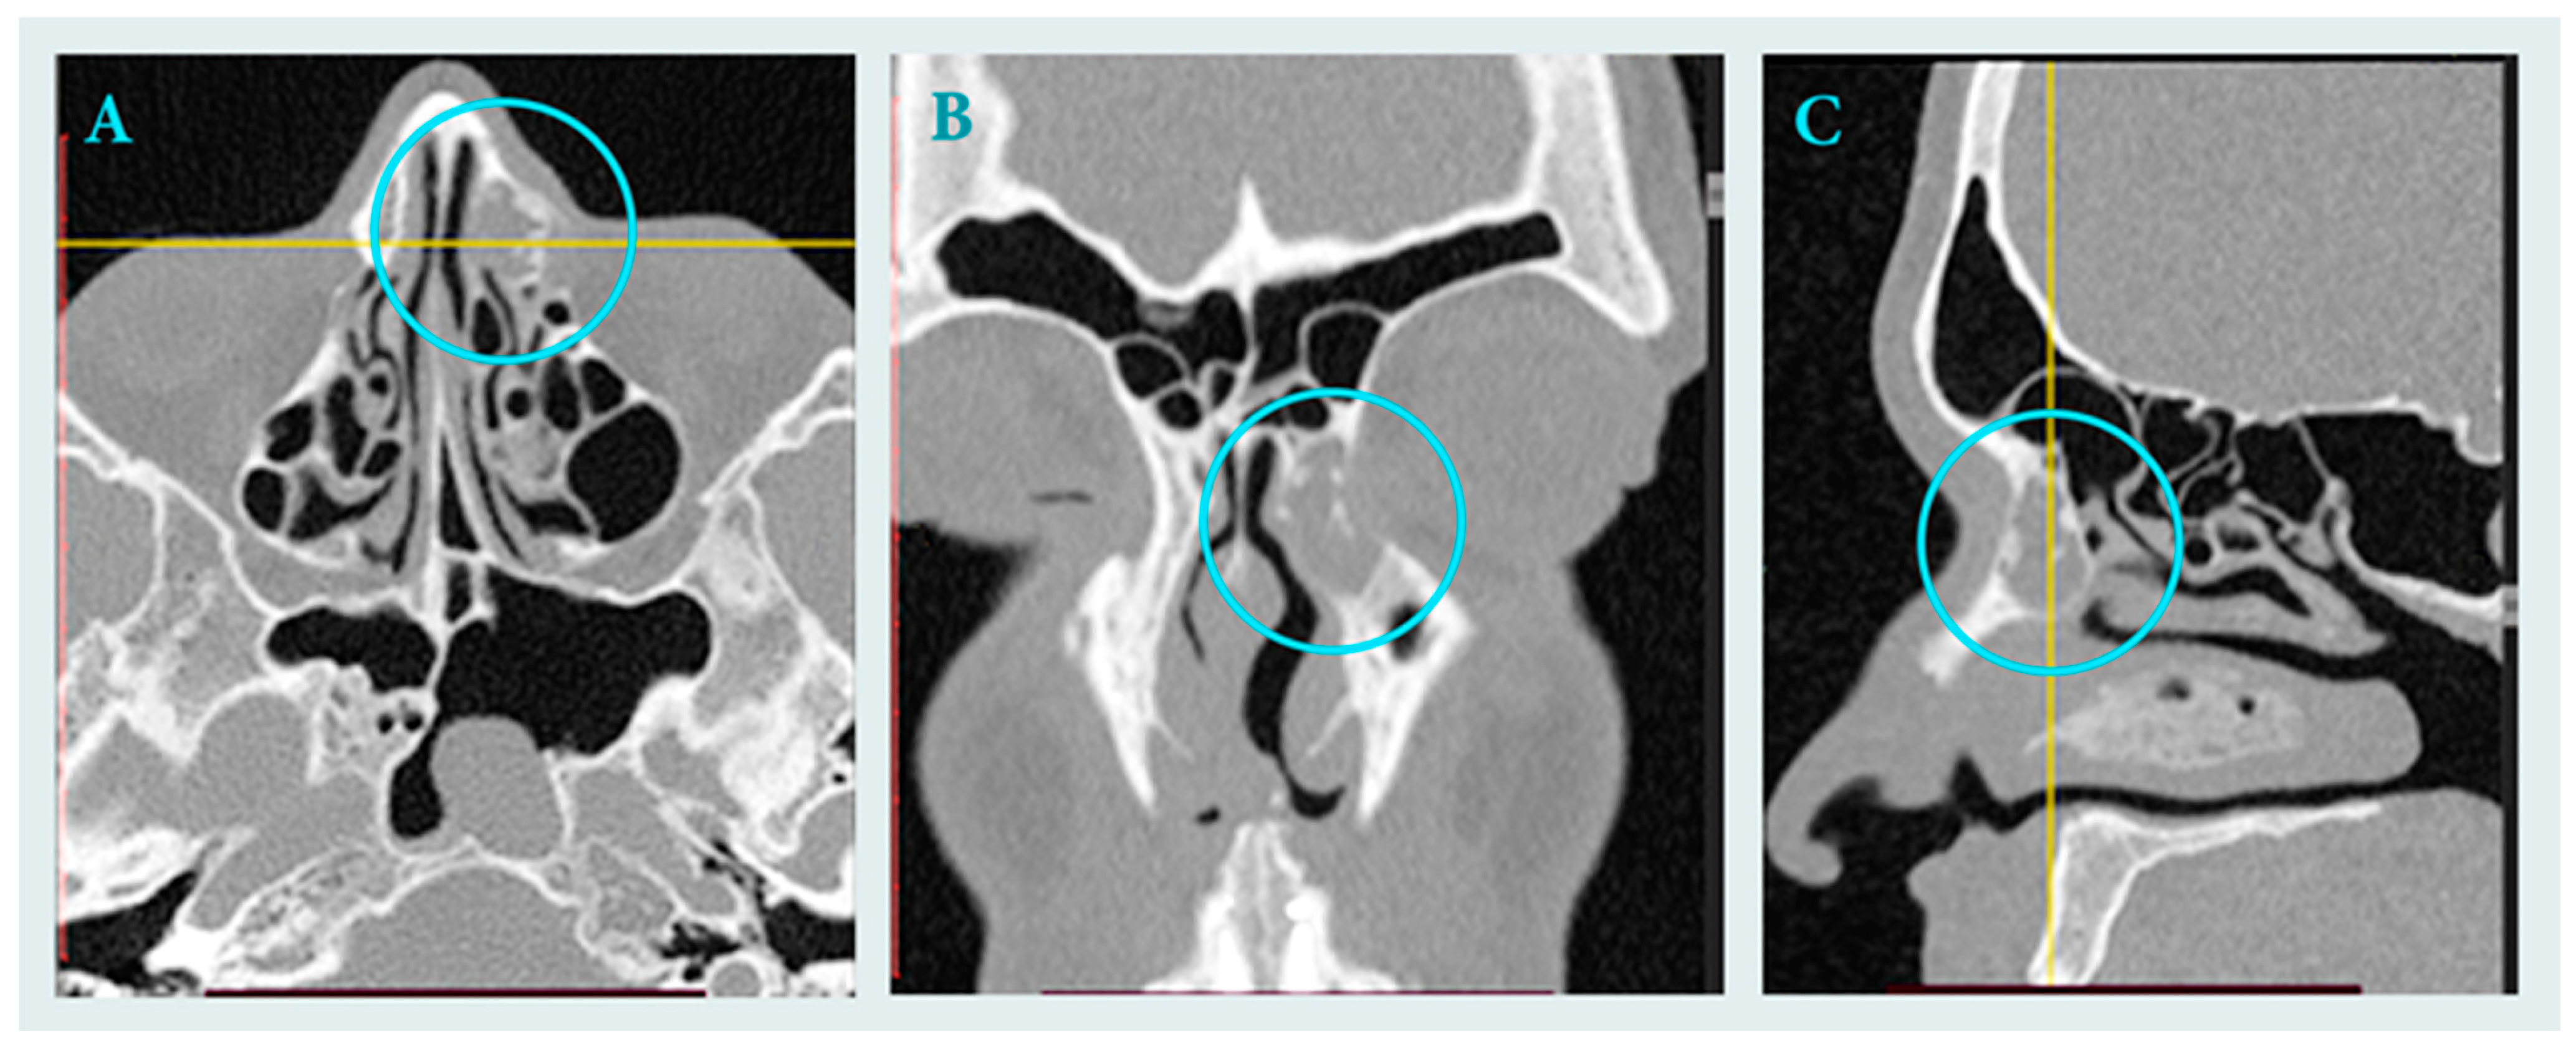

2.1. Clinical Data

2.2. Surgical Treatment